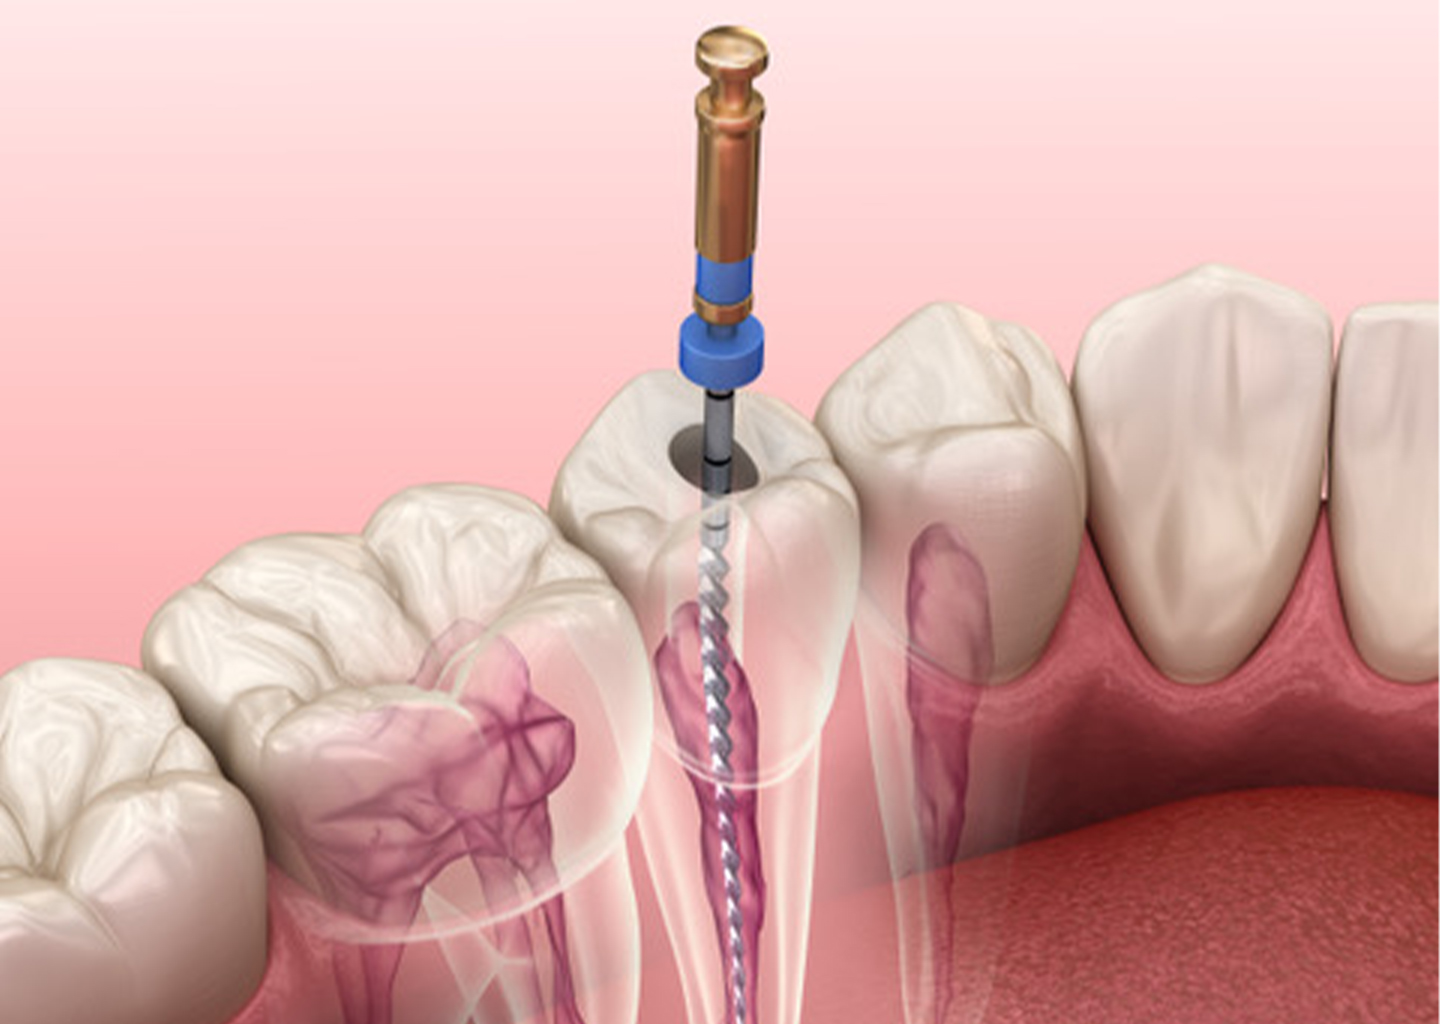

Zahnerhaltung

Unser Ziel ist es Ihre Zähne so lange wie möglich durch Prävention, Diagnostik und Therapie gesund und stark zu erhalten.